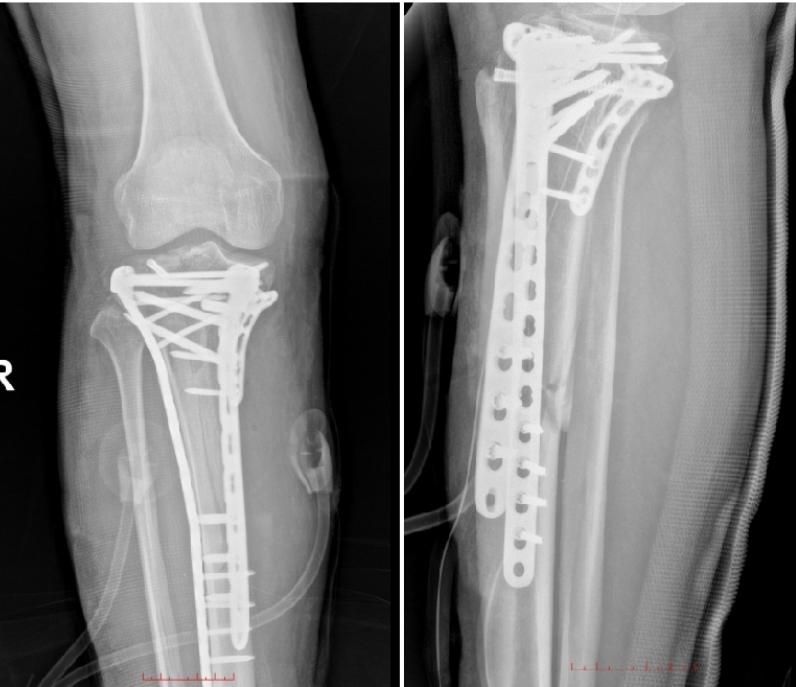

手术团队通过精准设计的双侧L型切口,充分暴露“碎裂现场”,开始进行精细的“骨拼图”:先将碎裂、塌陷的关节面一块块翘起复位,用克氏针临时固定;接着,根据骨折块的部位和形态,巧妙选用T型钢板、L型钢板以及全螺纹加压空心螺钉进行组合式固定,为碎裂的骨骼搭建起稳固的“内部脚手架”;精细缝合了撕裂的半月板和内侧副韧带。C臂X光透视可见骨折复位良好,关节面平整。为防止感染并促进伤口愈合,手术还应用了封闭负压引流技术(VSD),并在术后用石膏托妥善固定。手术历时4个多小时顺利完成,出血控制良好。

术后,王先生恢复情况良好,骨折部位对位精准,未出现皮肤坏死、感染、深静脉血栓等并发症。目前,王先生正在康复治疗师的指导下,循序渐进地开展膝关节功能锻炼,防止关节僵硬和肌肉萎缩。